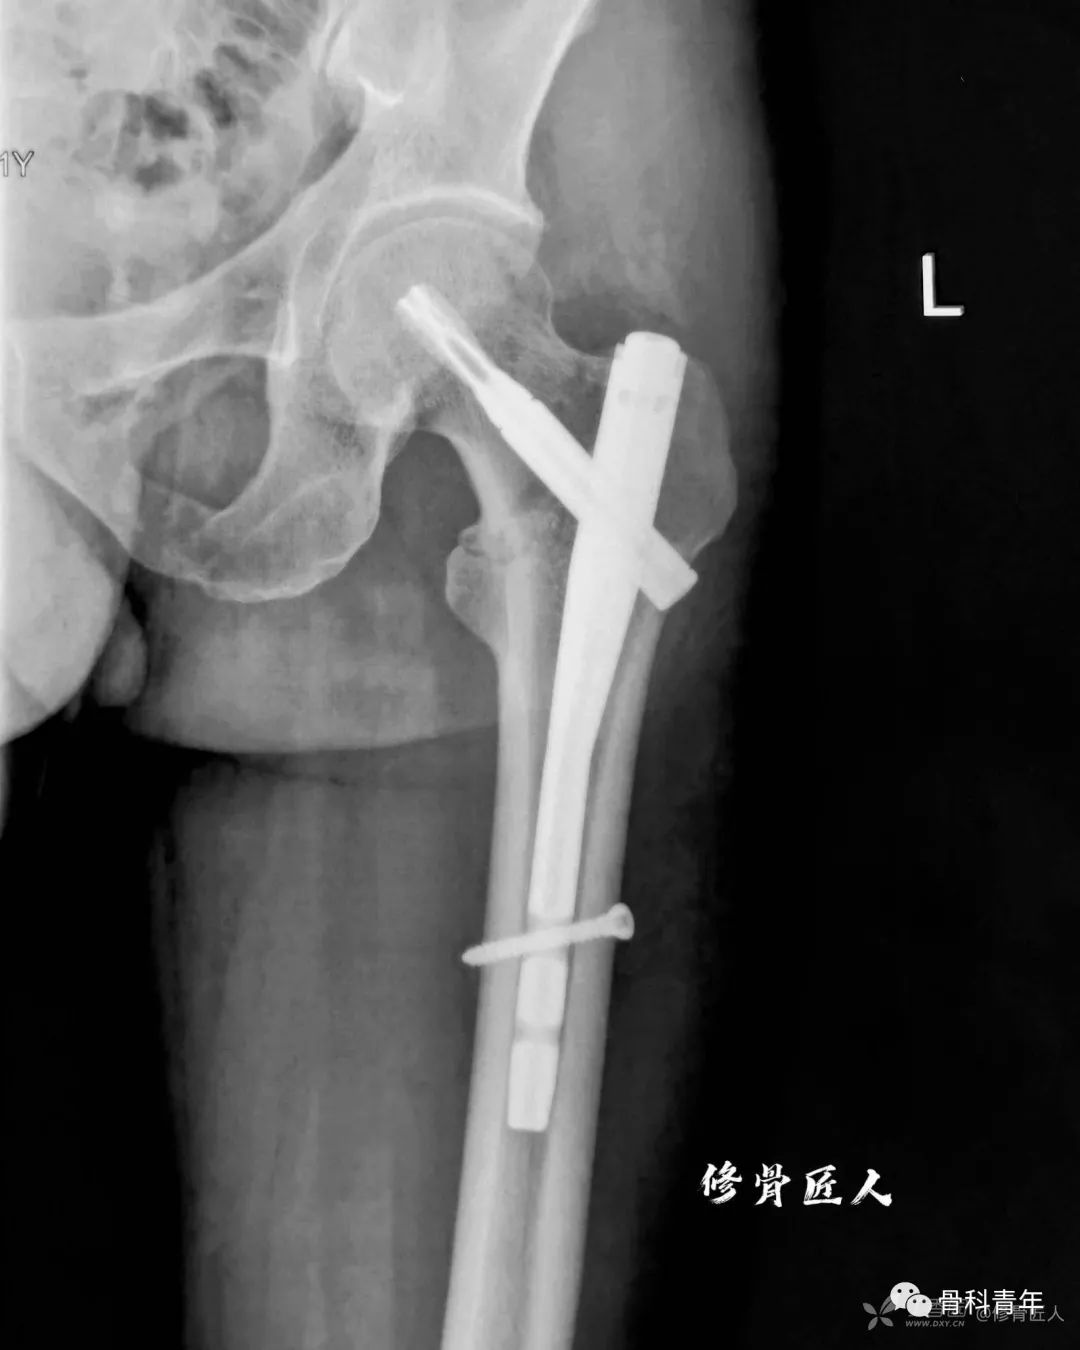

主钉钉尾突出大转子尖

主钉的钉尾在大转子的进钉点处,必须稍微突出一些,这样主钉在该部位的把持力,能避免股骨干的内移。

如果钉尾埋在松质骨中,它将摆动(toggle)、向内移动,最终导致不稳定、骨不连、内固定失败。

可以通过安装额外的尾帽,来使主钉钉尾突出于进针点之外。

在进针点没有固定作用的较短主钉,导致不受控制的内移、断钉。